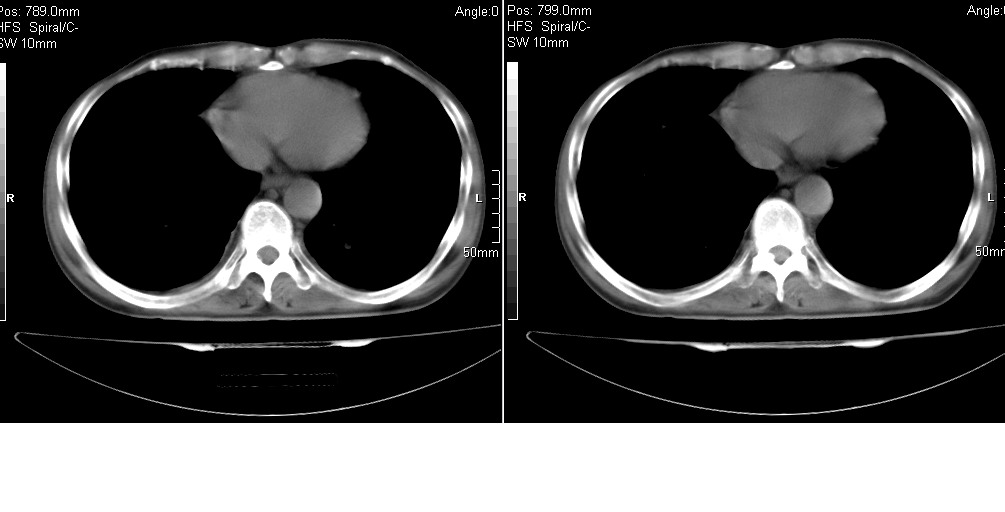

以下是引用光线在2008-5-6 18:36:00的发言:[br]双肺结核(左上肺空洞形成)、间质性改变合并感染,右肺大泡;右侧胸膜增厚。

以下是引用zsl6918在2008-5-7 1:54:00的发言:[br]首先肺泡蛋白质沉着症,其次考虑机遇性感染。